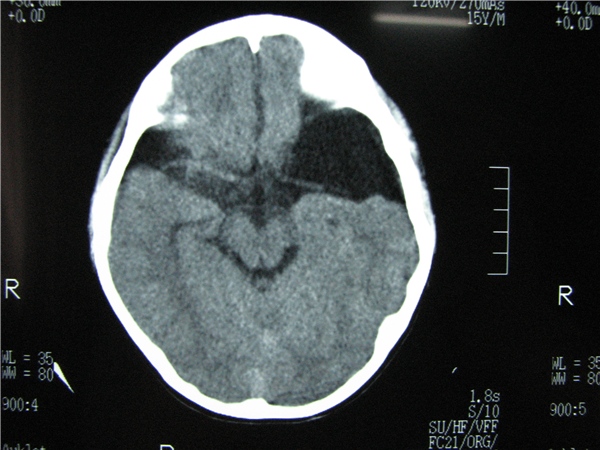

标题: CT20748:M 15Y 头痛,以前有外伤史请老师看看除了囊肿还有别 [打印本页]

标题: CT20748:M 15Y 头痛,以前有外伤史请老师看看除了囊肿还有别

m 15y 头痛,以前有外伤史请老师看看除了囊肿还有别的吗?

蛛网膜囊肿。眼拙,看不出别的,倒是看到了双侧大脑中动脉影,类似“致密动脉征”。

双侧侧裂池和纵裂池近前颅窝蛛网膜囊肿。

不能除外脑穿通畸形

无明显占位及负占位效应,考虑软化灶并脑室穿通畸形囊肿、局限性脑萎缩

蛛网膜囊肿,不能除外脑穿通畸形,支持。